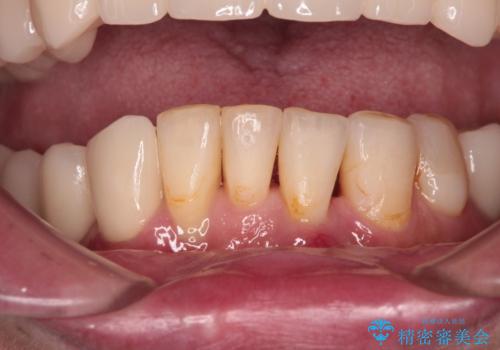

- 以前通院していた医院で、奥歯のインプラント埋入、前歯部のインビザライン矯正を行ったものの、そのまま放置してしまったとのことで来院された患者様です。

下顎前歯や上顎奥歯などをワイヤー装置により部分矯正を行い、歯列を整えた上でインプラン部分を含めてオールセラミッククラウンにて補綴治療を行うこととしました。

インプラント上の仮歯がボロボロになり、前歯に非常に負担のかかる状態であったため、早急に奥歯の仮歯を修復し、矯正治療、奥歯の補綴治療、前歯の補綴治療と順々に進めて行きました。